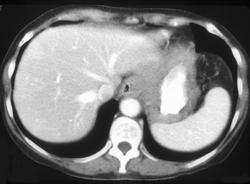

Left Upper Quadrant Abscess Within Necrotic Tumor